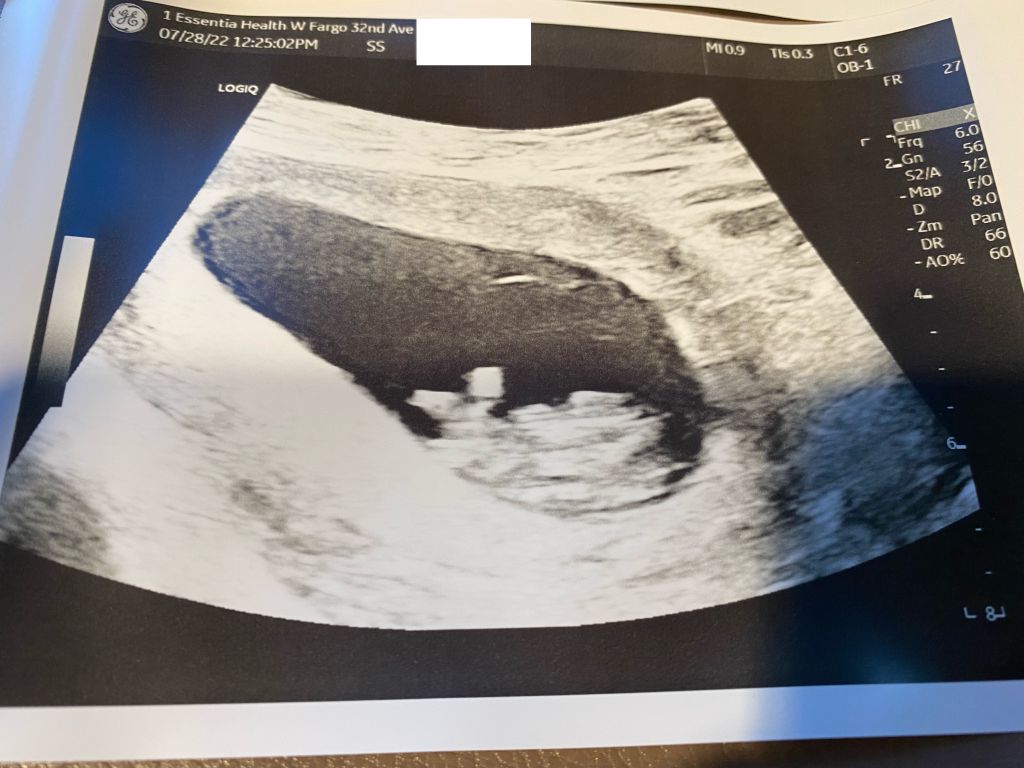

We just wanted to get a quick update out to keep everyone posted, but everything has been going very well still! On July 28th we met up with Jane in Fargo and had our second ultrasound, baby is measuring 9.5 weeks along at this appointment and is growing perfectly. We also received the news at this point that Jane will be released from ORMs directive and turned over to her own OB for the remainder of the pregnancy ๐ After the ultrasound, we were able to meet with the intake nurse at the hospital who was very informative and gave us some information to prepare us for baby’s arrival at their location. Jane also met with her OB a few days later, she was able to update us with an “official” due date of around 2/14/23 and also confirmed that the pregnancy is looking great!